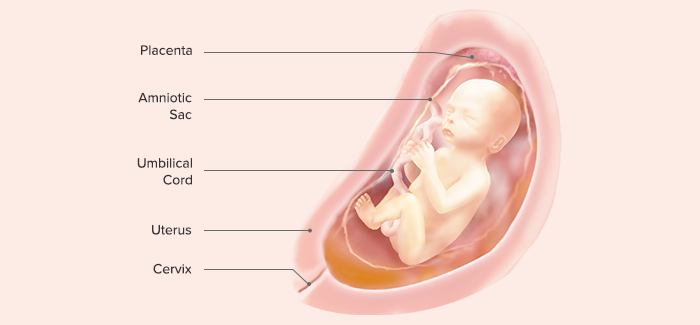

The placenta (Latin for “pancake,” which is descriptive of its size and appearance at term) arises out of the continuing growth of trophoblast tissue. Its growth parallels that of the fetus, growing from a few identifiable cells at the beginning of pregnancy to an organ 15 to 20 cm in diameter and 2 to 3 cm in-depth, covering about half the surface area of the internal uterus at term.

C. The Amniotic Membranes

D. The Amniotic Fluid

E. The Umbilical Cord

The umbilical cord is formed from the fetal membranes (amnion and chorion) and provides a circulatory pathway that connects the embryo to the chorionic villi of the placenta. Its function is to transport oxygen and nutrients to the fetus from the placenta and to return waste products from the fetus to the placenta. It is about 53 cm (21 in) in length at term and about 2 cm (3 ⁄4 in) thick. The bulk of the cord is a gelatinous mucopolysaccharide called Wharton’s jelly, which gives the cord body and prevents pressure on the vein and arteries that pass through it. The outer surface is covered with amniotic membrane.